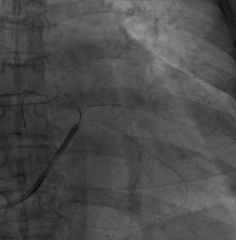

手术经过:首先冠脉造影延迟显影可见冠状窦开口及靶静脉大致走行

AP

LAO45